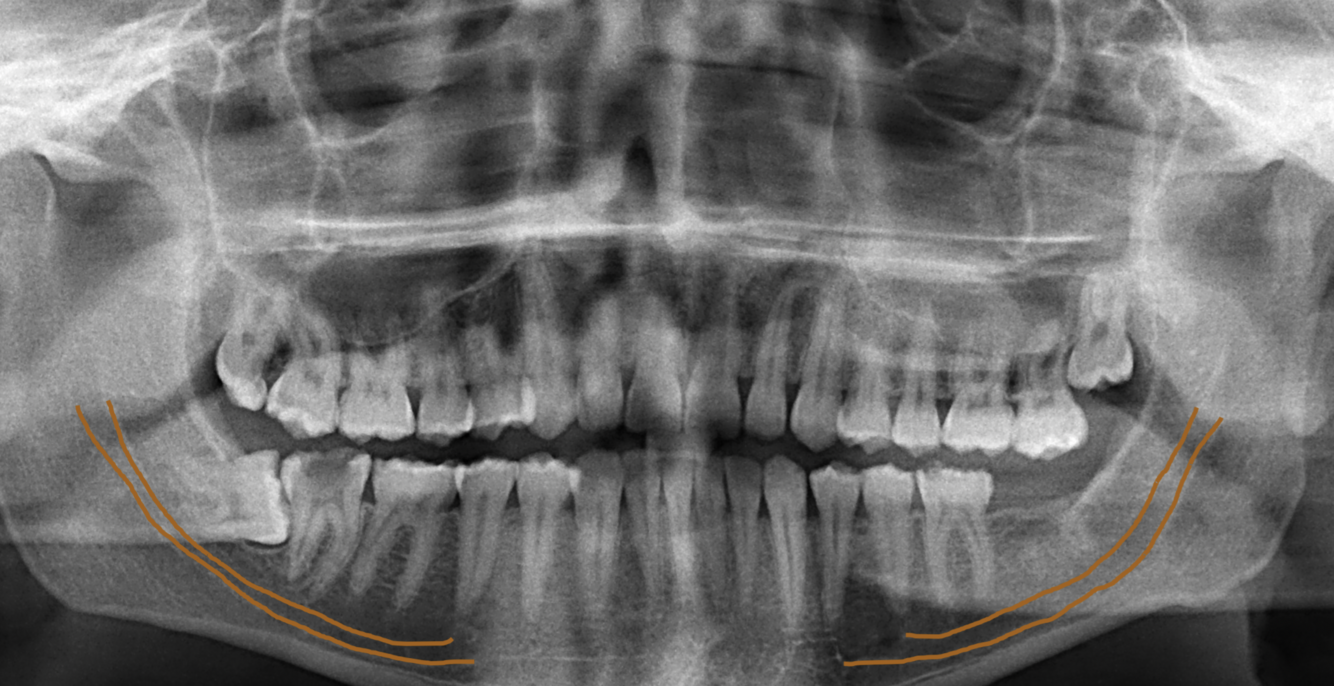

What does the orange indicate in the following image?

Submandibular gland fossa